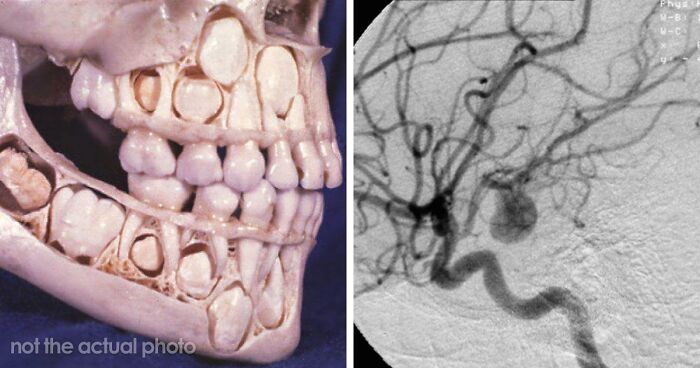

“Either God Or Evolution Is A Terrible Designer”: 59 Things That Freak People Out About Their Own Bodies

“Weirder Than Sci-Fi”: If You’re Looking For Something To Blow Your Mind Today, These 61 Scientific Facts Might Just Do It